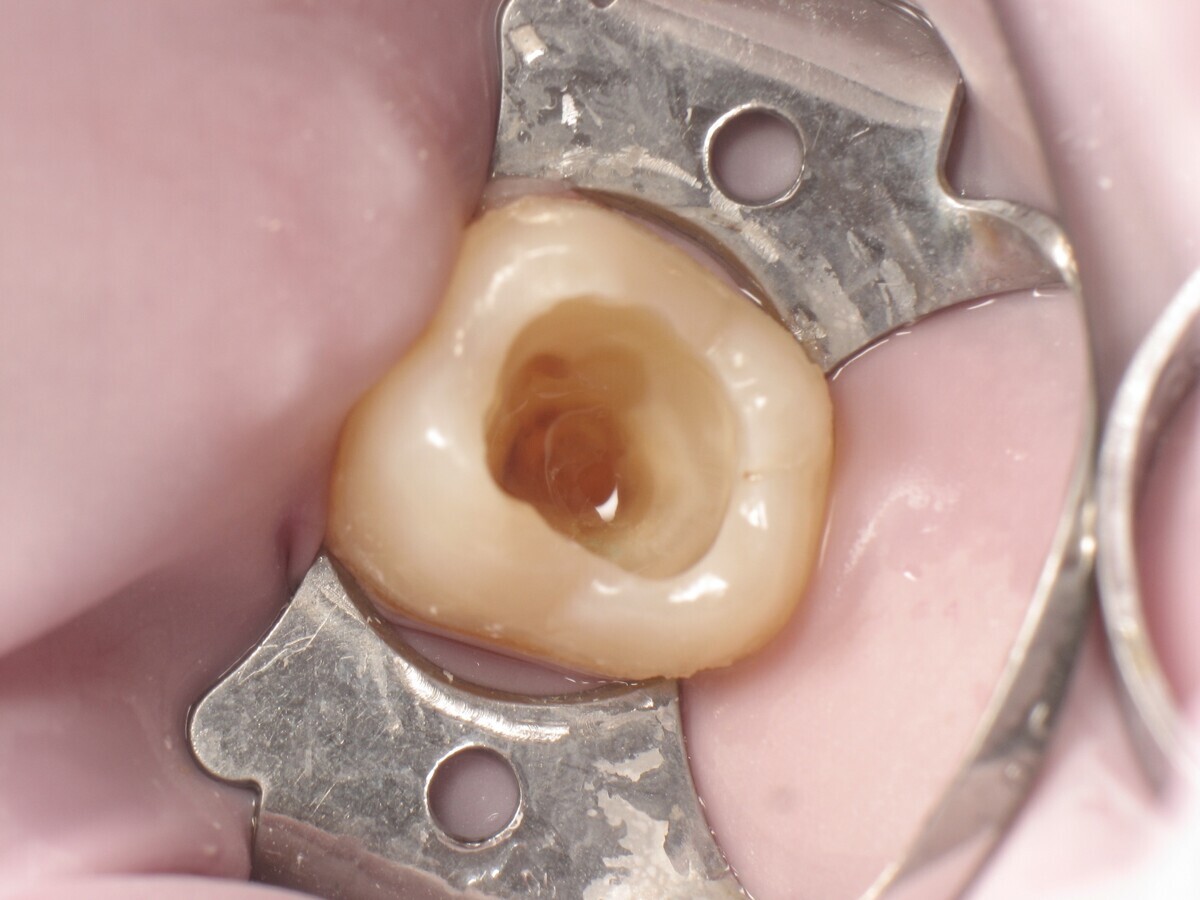

Este artículo describe el tratamiento de una cavidad clase I en un molar utilizando un composite termoviscoso mediante la técnica de la almohadilla (Figura 1). En primer lugar, se registran los detalles anatómicos utilizando una resina transparente, fluida y fotopolimerizable (Clip Flow, VOCO). El diente se aísla con un dique antes de aplicar el composite transparente a la superficie oclusal con un cepillo aplicador y fotopolimerizar durante 10 segundos (Figuras 2-4). La almohadilla oclusal así obtenida (Figura 5) debe almacenarse en alcohol (etanol o isopropanol) para eliminar la capa de inhibición. Luego se limpia la cavidad clase I (Figuras 6 y 7). A continuación se graba el esmalte durante 30 segundos y la dentina durante 15 segundos (Conditioner 36, Dentsply Sirona) y luego se enjuaga bien (Figuras 8 a 10). Debido al bajo espesor de la dentina remanente, también se aplica protección pulpar (Telio Desensitizer, Ivoclar Vivadent) (Figura 11). Luego se frota el adhesivo sobre las superficies dentales durante 20 segundos (Futurabond DC, VOCO), luego se seca bajo una pulverización de aire sin aceite graso durante 5 segundos y luego se fotopolimeriza durante 10 segundos (Figuras 12, 13). Para una humectación óptima, el fondo de la cavidad se cubre con un compuesto fluido de baja viscosidad (GrandioSO Light Flow, A3.5, VOCO) y se fotopolimeriza durante 20 segundos (Figuras 14, 15). Utilizando el Dispensador VisCalor, un dispensador portátil que permite el calentamiento y la aplicación simultánea de resinas, la cavidad se llena luego con un composite termoviscoso bulk (VisCalor Bulk, A2, VOCO).

Figura 07. Cavidad después de la excavación.

Figura 10. Cavidad después del enjuague y secado.